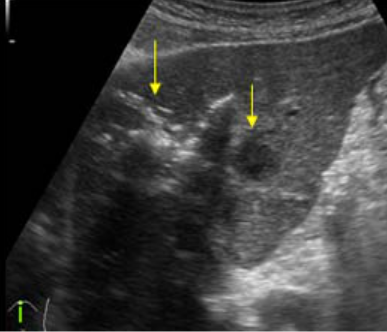

US finding

- 원형으로 경계가 분명한 단순낭종이다.

- 큰 낭종 안에 작은 낭종이 존재(daughter cyst)

- 낭종벽내 석회화가 관찰된다 (cyst wall calcification)

- 백합모양(water-lily sign)

daughter cyst and water-lily sign ②아메바성 간농양 (amoebic abscess)